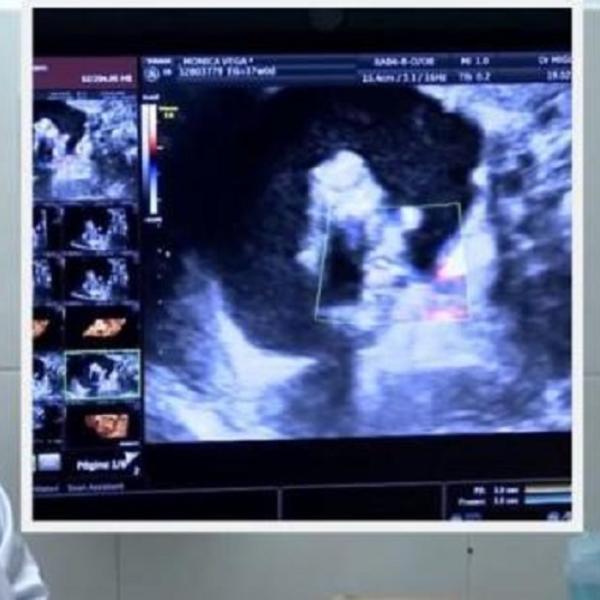

Lekari nisu bili optimisti kada je reč o Slađaninom zdravlju. Nakon dosta razmišljanja ipak su odlučili da je operišu, a operacija na kičmi je po njenim rečima trajala 12 sati.

-Kičma, kao i sve na meni je bilo izlomljeno, imala sam unutrašnje krvarenje. Bila sam nepokretna. Operacija je bila poslednja nada i pokušaj da me koliko toliko osposobe, a ja sam duboko u sebi znala da ću ostati živa. Rekli su mi da ću ostati invalid zauvek, a psihijatri i psiholozi su dolazili da me obilaze i pripreme na to. Amnezija me je okupirala 80% - priseća se Slađana.